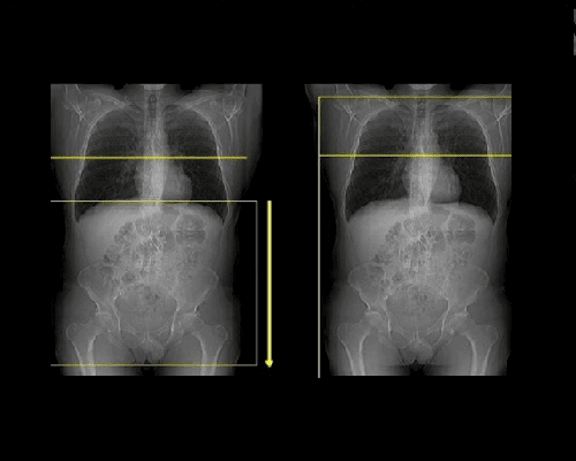

Перед исследованием рентгенолаборант устанавливает пациенту внутривенный периферический катетер. Проводится стандартное исследование органов брюшной полости и забрюшинного пространства без контрастирования, далее вводится контрастное вещество внутривенно с помощью инжектора и одновременно проводится постконтрастное сканирование.

Перед КТ исследованием необходимо пройти контрастирование желудка и тонкой кишки. Процедура требует подготовки. В течение 40-60 минут пациент должен выпить небольшими глотками один литр негазированной воды с йодосодержащим контрастом. При наличии повышенной чувствительности к йодсодержащим препаратам, аллергических реакций в анамнезе на введение йодсодержащих препаратов йодсодержащие вещества к воде не добавляется.